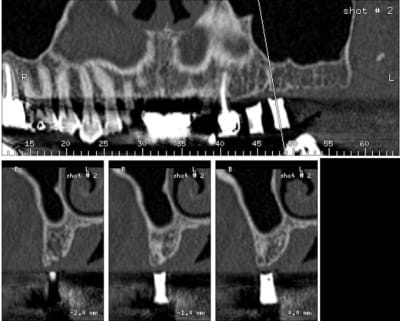

j'effectue demain mon premier Summers

et je suis presque près, à part une question

de dernière minute que je vous soumets en urgence:

comment se répérer sur le forêt pilote pour une profondeur de forage de 4 mm ?

la première graduation est à 7 mm, et les jauges ne se vissent pas si bas

avez-vous un truc ? ( à part l'estimation visuelle )

ci-joint scan pour les curieux

je pensais faire un aplanissement de crête jusqu'à une largeur de 7 mm pour un WP

évidemment, sans aplanissement, on a 7 mm au forêt pilote,

mais par la suite, je perds la distance de travail au fur et à mesure que les diamètres croissent, la distance diminue

( voir scan )

apparement, sur ton image, tu as bel et bien 7 à 8 mm d'os.

donc, tu fores à 7 avec un stop, si tu veux aplanir, tu le fais ensuite.

il me semble que tu as largement la place pour un 8mm et même un 10mm en perforant le sinus avec ou sans summers.